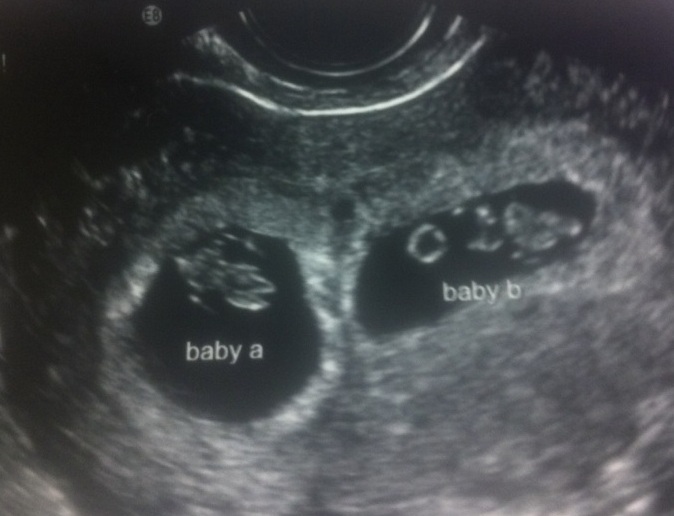

This is the week 7 sonogram we found out we were having twins. My husband Chris was speechless for about 10 minutes, and then he celebrated.

To be honest, we had no expectations that it would work. My body was not producing enough estrogen to ovulate, so my doctor prescribed Clomid* to encourage my ovaries to drop an egg. Studies show that about 30 percent women taking Clomid conceive. Of these pregnancies, 7.8 percent resulted in multiple births because of the ovary-stimulating effects of the drug. We are blessed that it only took 1 round.